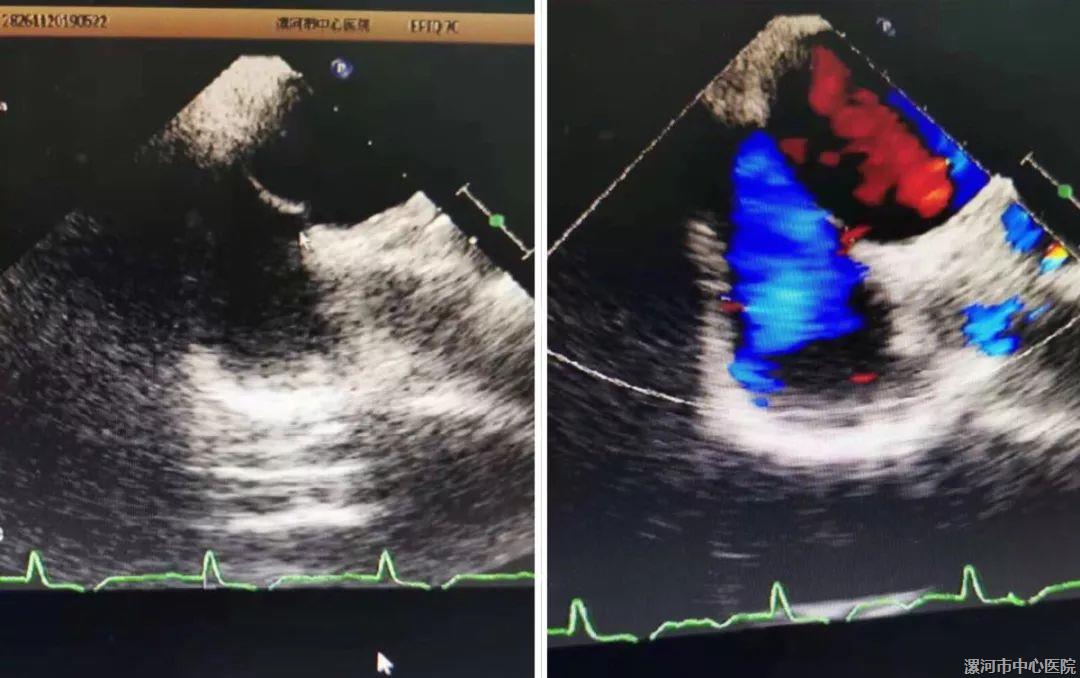

术前超声下显示卵圆孔未闭,可见右向左分流

患者为33岁男性,因“突发头晕、恶心呕吐”入住医院心内科一病区接受治疗,查头颅磁共振提示双侧小脑急性脑梗死,考虑不明原因卒中,行经食道超声心动图证实房间隔膨胀瘤并房间隔右向左分流(right-to-left shunt,RLS)。经心内科、神经内科、超声诊断科、介入科等多学科专家联合会诊后,专家们一致认为,患者的病情最适合卵圆孔未闭(patent foremen ovale,PFO)封堵术。